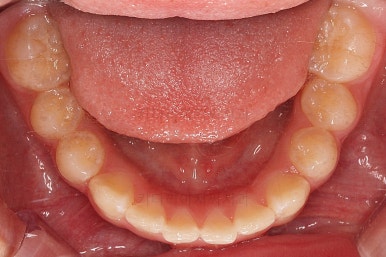

초진 시 입안의 모습입니다.

앞니가 안으로 굽어 들어간 양상인데요. 흔히 "옥니"라고 표현합니다.(뻐드렁니의 반대개념)

전반적으로 치열이 삐뚤삐뚤하고요.

오른쪽 상단 사진을 보시면 어금니의 높이와 앞니의 높이가 차이가 많이 납니다.

앞니가 솟구쳐 있는 양상인데요.

그 이유 때문에 어금니로 다물었을 때의 위아래 앞니가 많이 겹쳐서 아래 앞니가 아예 보이지 않는 상황이었어요.

이를 "과개교합"이라고 표현합니다.

그리고 전반적으로 아래 치열이 윗니에 비해 뒤로 밀려 있어서, 어금니의 맞물림이 좋지 못하고 듬성듬성해 보이는 상황이었어요.